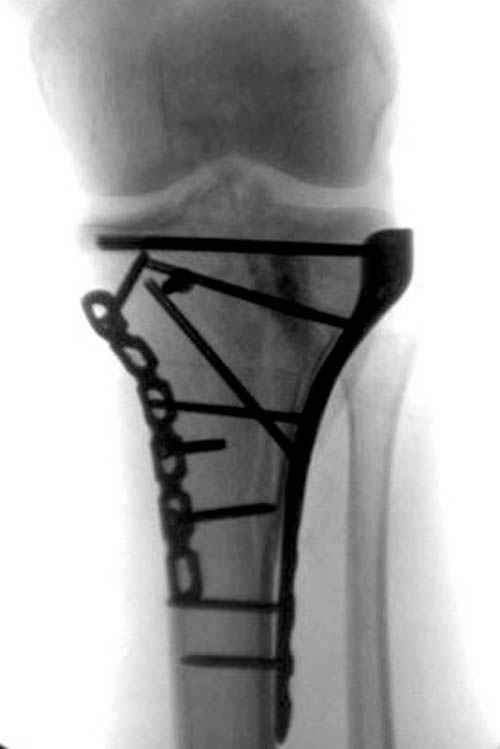

Такая ситуация характерна для многих, когда принимается ошибочное решение, т.е пытаются фиксировать одним имплантом переломы двух мыщелков. Латеральная пластина приемлема только для тех случаев, когда сохраняется интактным медиальный диафизарный кортекс и отсутствует фрагментация на верхушке медиального перелома.

При сложных переломах тибиал плато для своего рода Damage Control мы иногда применяем поэтапную тактику. Сперва оперируется одна сторона, а потом после рекондиции мягких тканей окончательный этап.

Если состояние мягких тканей позволяет, я бы предложил такой метод для вашего больного. Без предварительного планирования будет трудно, но шанс не надо упускать. Всего несколько дней после операции, и такая тактика лучше, чем недовольный молодой пациент.

Доступ к медиальной стороне задний или медиальный, через pes или в пространстве между medial gastroc мышцы.

Надеюсь, представленные снимки разных случаев помогут разобраться в тактике, и критика примется без личной обиды.